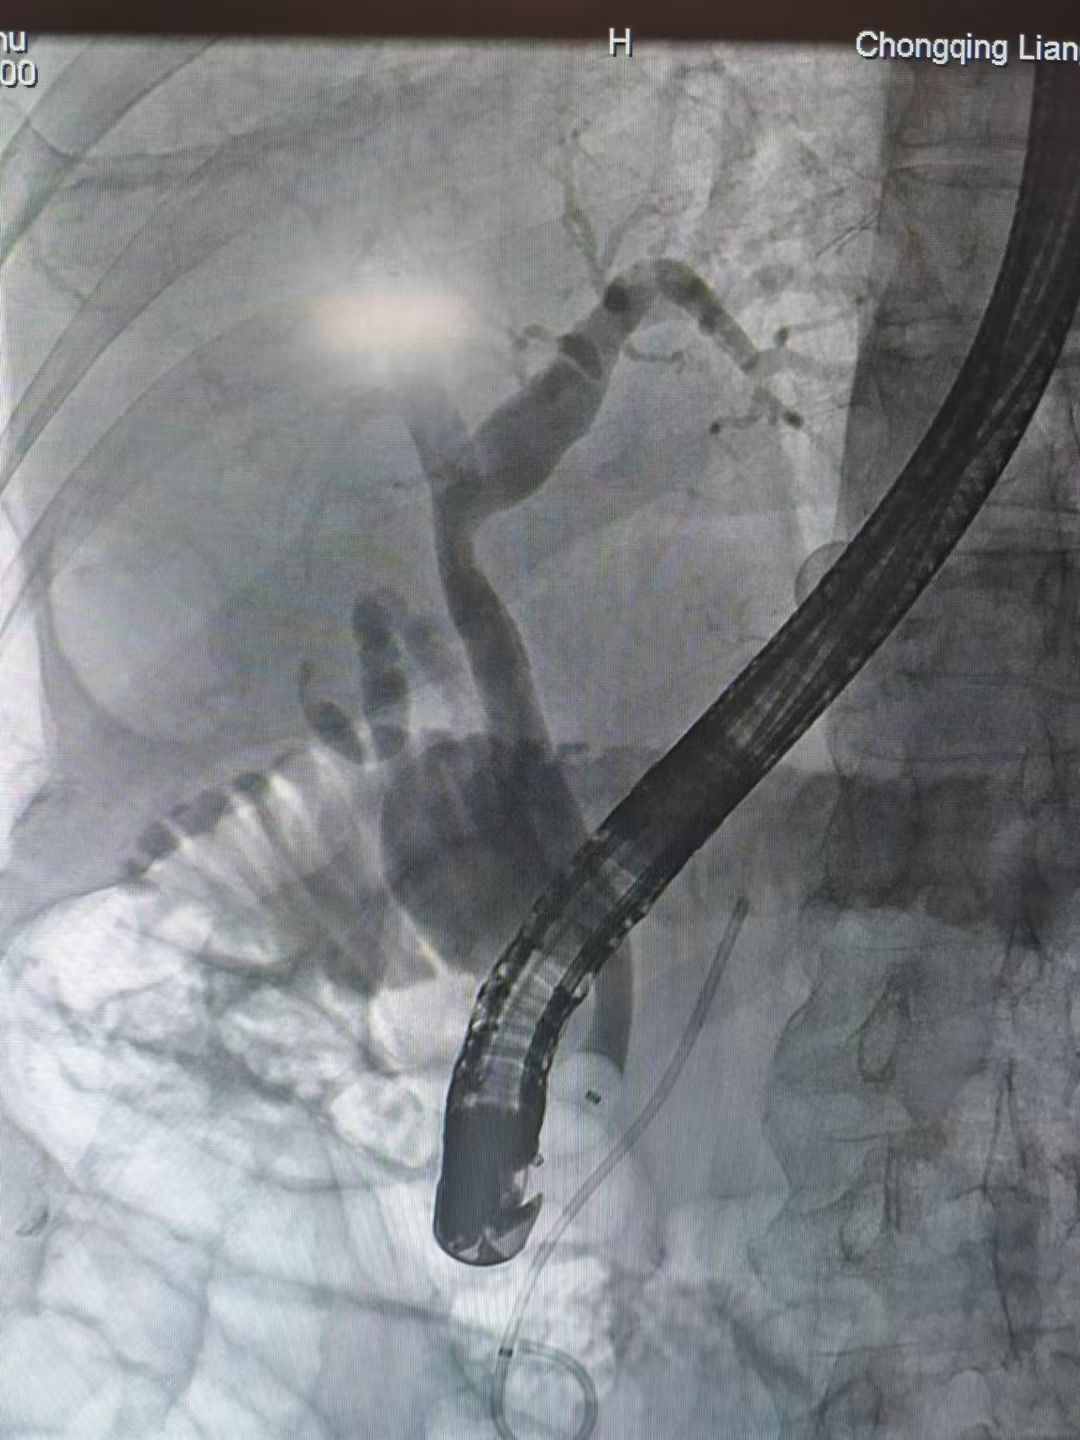

5日后,唐大爷的感染症状得到完全控制,决定开展二次手术,通过ERCP明确胆道病变情况,然后利用球囊扩张术扩大胆道开口,再根据结石的具体情况选择网篮碎石术、网篮取石术或球囊取石术将结石取出。最后通过ENBD(内镜下鼻胆管引流术)进行胆汁引流,确保胆道通畅,防止并发症的发生。

整个手术过程平稳,患者痛苦小,出血量少,术后恢复迅速,避免了传统手术大切口带来的疼痛和较长的恢复期等问题,也为同龄胆道疾病患者提供了新的治疗途径。